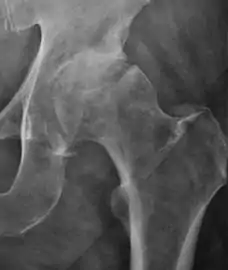

Osteoarthritis

In adults, one of the main indications for radiographs is the detection of osteoarthritic changes (Figure 1(e)). Nevertheless, radiographs usually detect advanced osteoarthritis that can be graded according to the Tönnis classifications. The grading system ranges from 0 to 3, where 0 shows no sign of osteoarthritis. Intermediate grade 1 shows mild sclerosis of the head and acetabulum, slight joint space narrowing, and marginal osteophyte lipping. Grade 2 presents with small cysts in the femoral head or acetabulum, moderate joint space narrowing, and moderate loss of sphericity of the femoral head. Grade 3 is the severest form of osteoarthritis, which manifests as severe narrowing of the joint space, large subchondral cyst with productive bone changes that may lead to deformity of the bone components of the joint, while secondary osteoarthritis due to calcium pyrophosphate deposition can be diagnosed when calcification of hyaline cartilage and fibrocartilage is detected.[1]

There are other pathological conditions that can affect the hip joint and radiographs help to make the appropriate diagnosis. Acute bacterial septic arthritis can be diagnosed by radiographs when a fast regional osteoporosis and destructive monoarticular process develops (Figure 1(f)). In case of tuberculous or brucella arthritis it is manifested as a slow progressive process, and diagnosis may be delayed.[1]